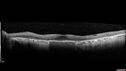

Concentric Geographic Atrophy - 76 YO male

76 year old man The patient has noticed that his vision is getting worse at night. The vision loss has come on gradually. He notices that his vision in low lighting is poor and at night with oncoming headlights.

Concentric Geographic Atrophy - 76 year old man359 viewsGradual vision loss, worse at night. VA 20/40 OU.     (0 votes)